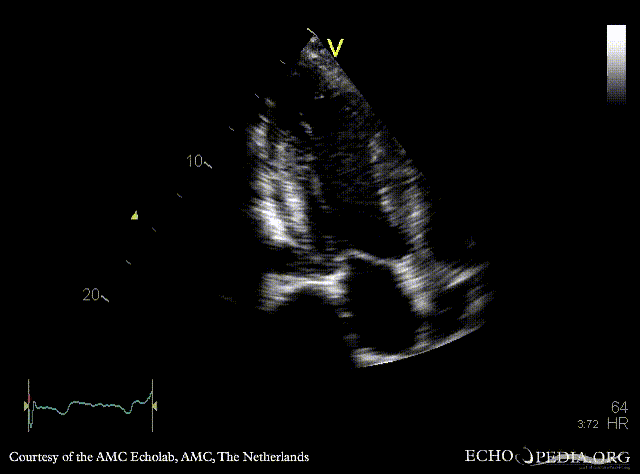

Subvalvular membrane in left ventricle outflow tract

A3CH A3CH with Color Doppler